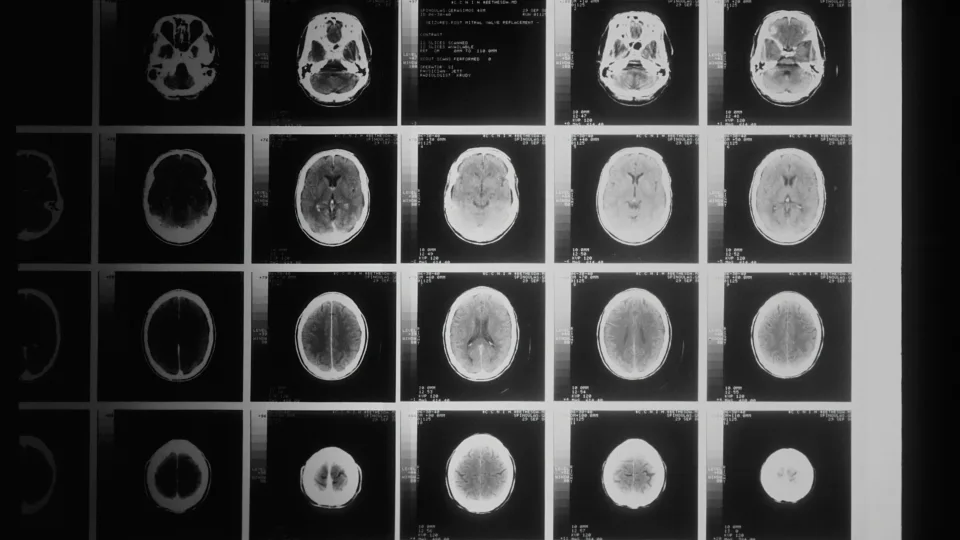

Smegenys keičia formą: mokslininkai rado ženklą, kuris išduoda artėjančią demenciją dar iki simptomų

Mokslininkai vis dažniau kalba apie tai, kad demencijos požymiai gali pasirodyti gerokai anksčiau nei prasideda akivaizdūs atminties sutrikimai. Naujausi tyrimai rodo, kad užuominų apie būsimą ligą galima rasti pačioje smegenų struktūroje.

Analizuodami daugiau nei du su puse tūkstančio magnetinio rezonanso tyrimų, jie pastebėjo aiškius skirtumus tarp sveikų žmonių ir tų, kurių kognityviniai gebėjimai jau silpnėjo. Šie atradimai suteikia pagrindo tikėtis, kad smegenų geometrija taps nauju medicinos įrankiu.